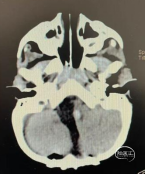

术前头部CT

脑干与小脑半球可见一团片状密度增高影,大小约46*51*55mm3边界欠清,内可见班点状钙化灶,病灶突入四脑室内,第四脑室受压变窄,脑室系统扩张明显。肺部CT:双肺可见多发斑片状片状密度增高灶,边界欠清,以右肺为甚,部分病灶内可见支气管充气征;叶间裂无移位,气管支气管通畅。